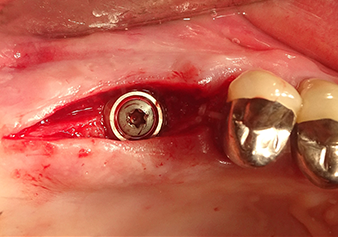

Après un contrôle intermédiaire (Fig. 4), une étape de préparation ultérieure est exécutée (Fig. 5). Puis on utilise l’insert Z35P hydraulique pour relever la membrane vers la position souhaitée (Fig. 6 et 7). Ensuite, une préparation piézochirurgicale supplémentaire est pratiquée sur le site implantaire, en utilisant pour terminer un burin rotatif et une fraise à épaulement jusqu’à 4,8 mm de diamètre d'implant. Avant l’insertion de l'implant, le matériau d’augmentation (taille de particules env. 0,8-1,6 mm) est introduit sous la membrane de Schneider (Fig. 8).

Implantation et restauration prothétique

Pour mettre en place le matériau d’augmentation en douceur en direction du sinus maxillaire, l’implant est inséré manuellement très lentement (Fig. 9). Pendant l’opération, la membrane est poussée de nouveau dans la direction crânienne. Au bout de deux mois, le site chirurgical cicatrise sans signes d’irritation. Six mois plus tard, la radio de contrôle révèle une augmentation significative de l'opacité indicative de l’ossification (Fig. 10). La restauration prothétique est réalisée avec une couronne métallo-céramique.

Les augmentations de plancher sinusien interne sont traditionnellement effectuées à l'aide d’instruments manuels, en associant un effet de martèlement à une préparation du site implantaire par des moyens rotatifs. L'expérience a appris à l’auteur que les systèmes piézochirurgicaux modernes rendent cette procédure nettement moins traumatique car l’effet de cavitation permet une utilisation pratiquement sans pression. Les inserts sont utilisés d’une part pour la préparation du site implantaire et pour pratiquer une ouverture minimalement invasive dans le plancher du sinus maxillaire, et d’autre part, pour l’élévation hydrodynamique de la membrane de Schneider [8].

Dans la pratique de l'auteur, l’élévation de la membrane est généralement opérée en deux phases. Mais la technique spécifiée par le fabricant est également adaptée. Dans ce cas, le site implantaire est d'abord préparé et, dans un second temps seulement, une petite ouverture est pratiquée dans le plancher du sinus osseux à l'aide de l'insert Z35P. Grâce à cette méthode particulièrement atraumatique, la patiente n'a ressenti aucune douleur postopératoire et a pu retourner au travail dès le lendemain. Au cabinet de l’auteur, ce résultat est obtenu chez 90 % des patients.